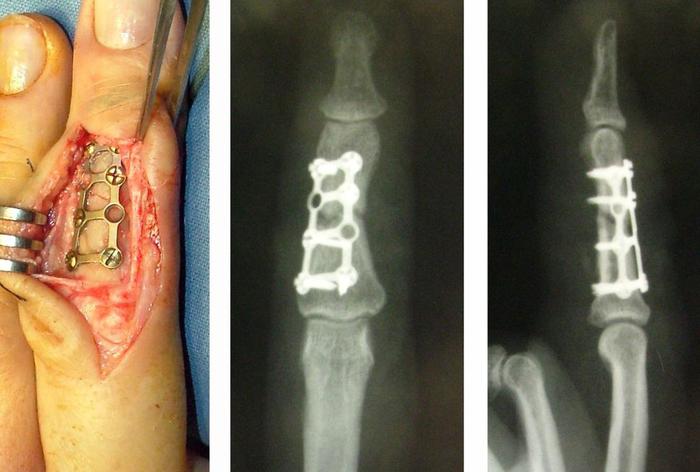

При наличии смещения, необходимо хирургическое вмешательство – остеосинтез (фиксирование отломков).

При переломах со смещением чаще всего применяется фиксация, варианты могут включать: использование штифтов через кожу (которые остаются снаружи), пластины и/или винты, устанавливаемые через разрез. Начать двигать суставами пальца можно через несколько дней после операции.

При переломах основания или головки фаланги чаще всего фиксация происходит с помощью штифтов или винтов, тогда как при переломах диафиза применяются винты или пластины. В случае многооскольчатых переломов может быть использован аппарат внешней фиксации.

Как правило, после операции гипсовая лонгета не накладывается, за исключением сложных нестабильных оскольчатых переломов.

Конкретный метод остеосинтеза выбирает лечащий врач с учетом клинической ситуации, характера смещения и требований к функции кисти.